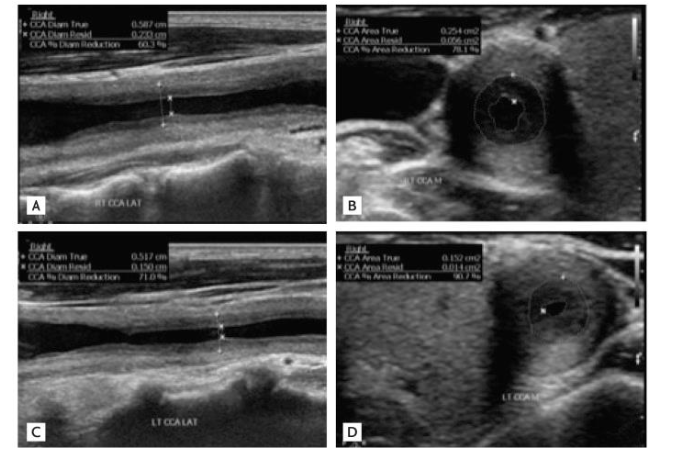

Whats FMD, fibromuscular dysplasia, what does it mostly affect

more likely in young women (25-50)

usually occurs in the ICA, renal artery, brachial, iliac and femoral

FMD is an overgrowth of the smooth muscle cells and fibrous tissue in muscle walls

patients usually have HTN due to decreased renal artery blood flow

has a string of pearls appearance, occurs mid to distal vessel, at least 1 cm from bifur. creates tandem stenosis effect within vessel. Common differential with vessel tortuosity.